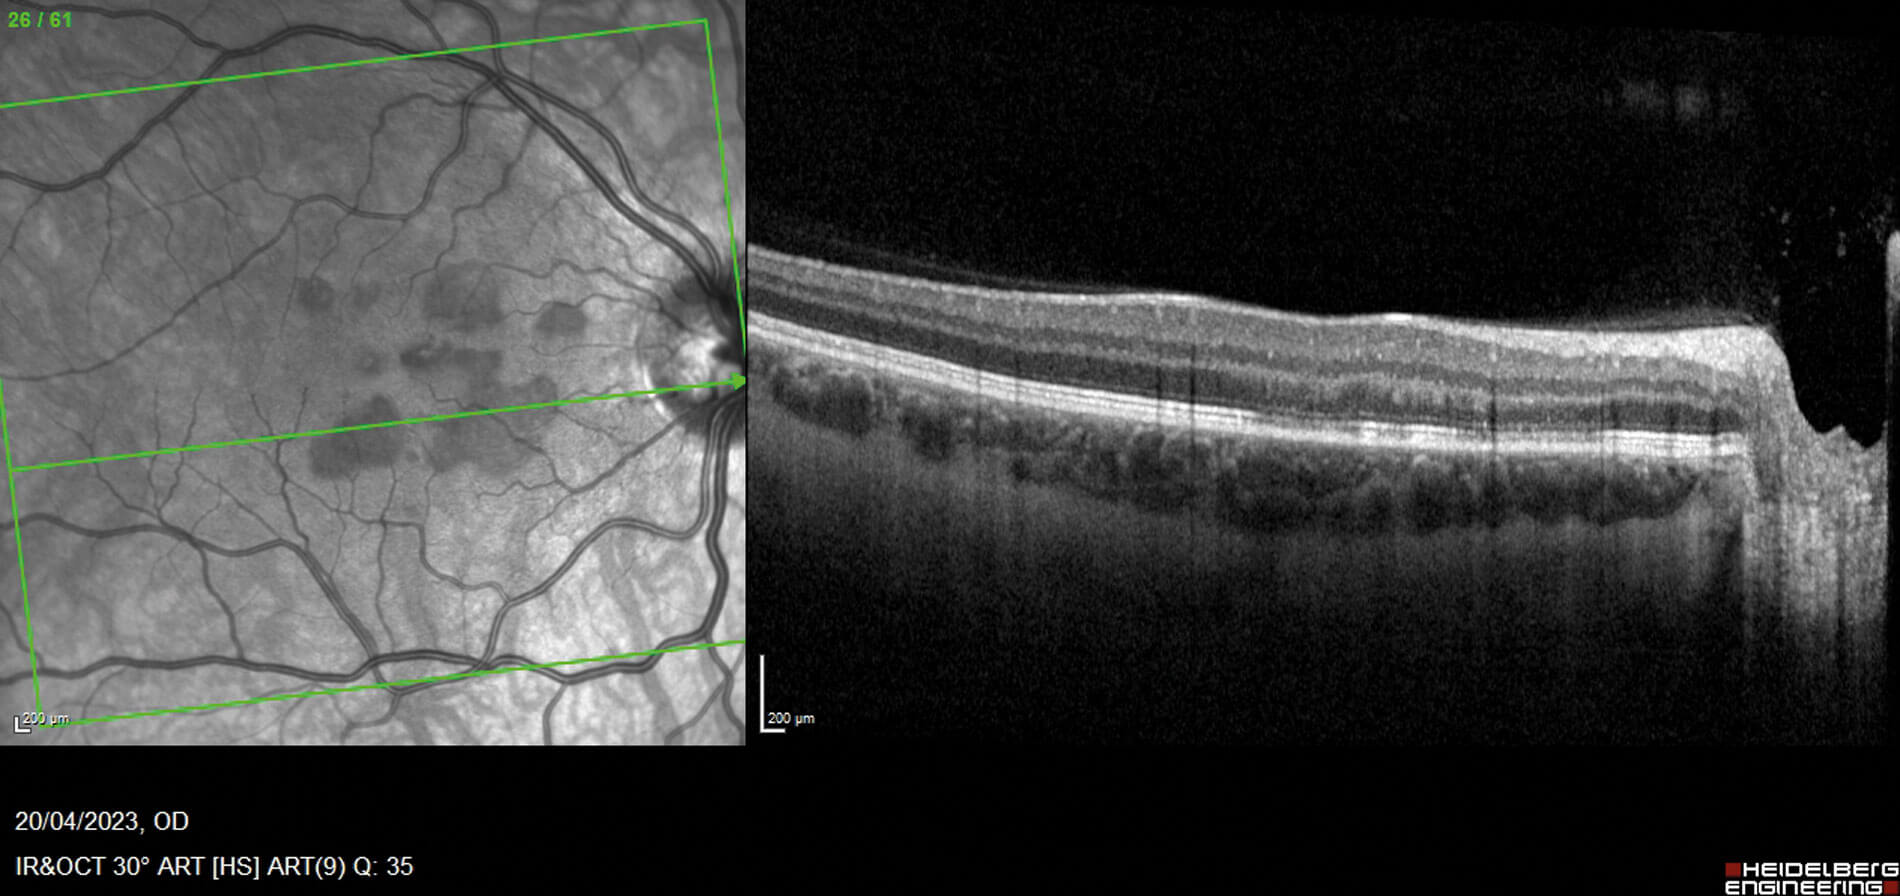

Figures 1a (top) and 1b (bottom): OCT macular view, showing hyper-reflectivity in the outer nuclear layer, with associated focal signal reduction of the inner segment / outer segment junction in the left eye (a) and right eye (b). Near infrared pictures show corresponding areas as mostly petaloid lesions, pointing towards the fovea.

Fundoscopy showed evidence of discrete foveal reflex changes, which on further evaluation with optical coherence tomography (OCT) macular view showed multiple areas of outer retinal disruption (see Figures 1a and 1b). Optical coherence tomography angiography displayed evidence of reduced flow in the deep retinal plexus, consistent with ischaemia (Figures 2a and 2b). These retinal imaging findings correlated with the patient’s subjective visual changes, as noted on their Amsler grid drawings (see Figures 3a and 3b).